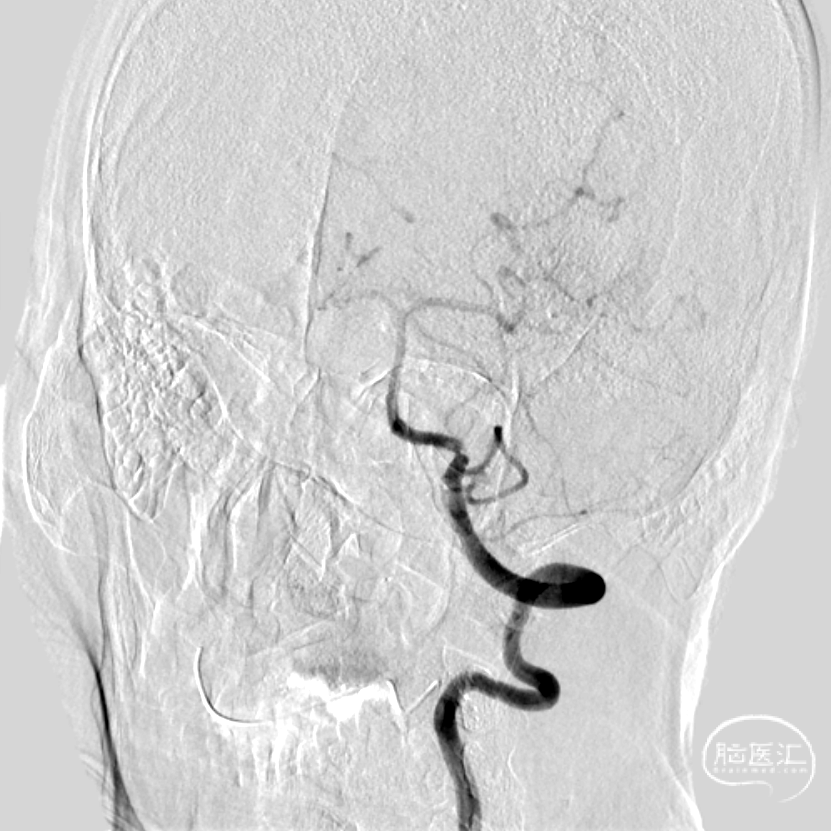

➢ 颅脑DSA

② 椎动脉狭窄(左侧V4段,重度)

正侧位颅内造影:前向血流显影减淡,左侧大脑后动脉栓塞再通。

重度狭窄处可见夹层改变。

正侧位颅内造影。

术前术后血管病变处对比。